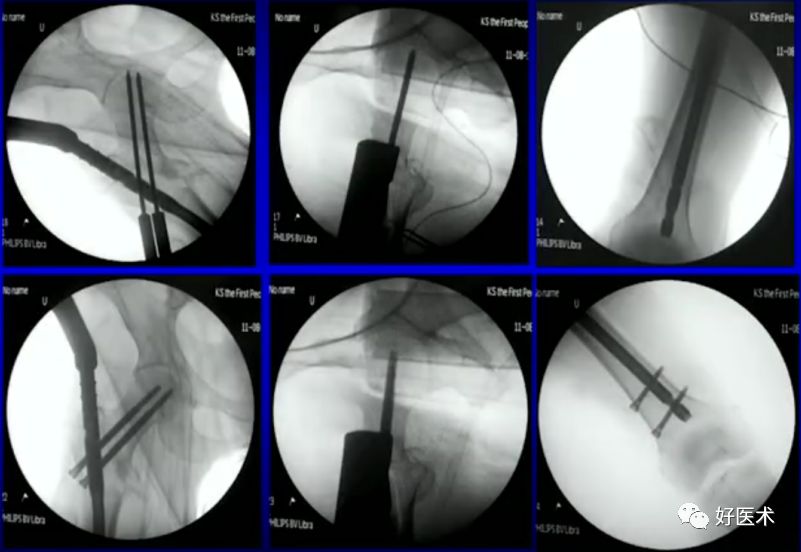

1.撬拨技术

用克氏针或斯氏针对移位的骨折块进行撬拨复位。

病例一:女 94岁

体表定位与撬棒置顶

撬棒置顶后内收情况

正位进针位置调整情况

主钉插入后的导针正侧位

病例二:女 75岁

术前复位:

定位:

术后: